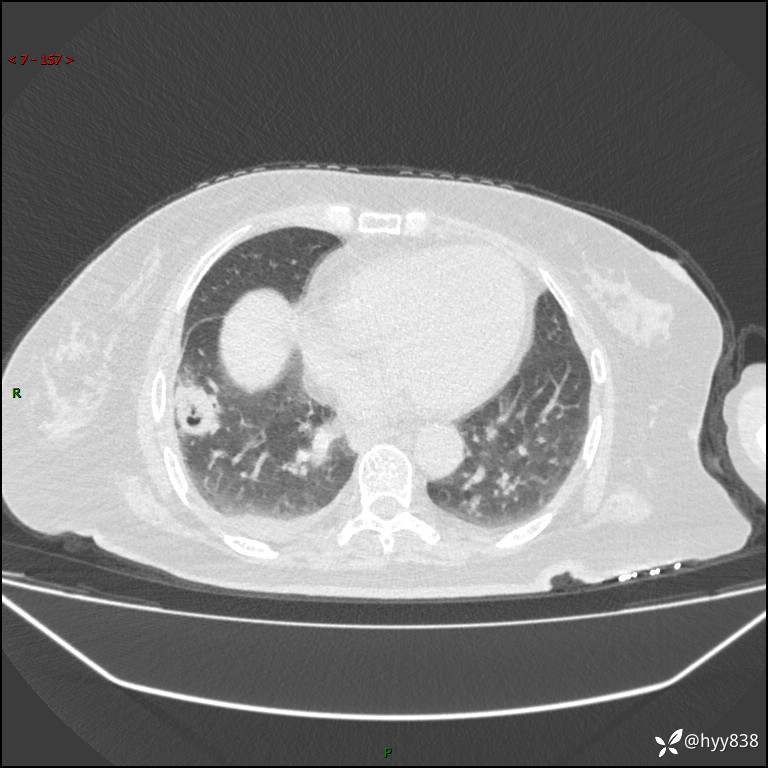

患者性别:女

患者年龄:57岁

简要病史:昏迷入院

临床诊断:昏迷

胸部 CT平扫、